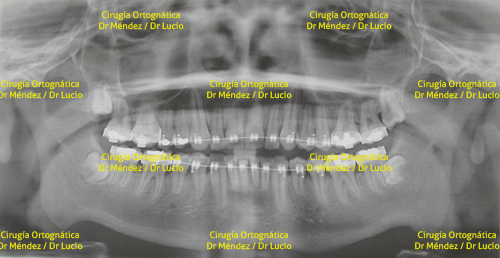

RETROGNASIA E HIPOPLASIA DEL MENTÓN Paciente operado de avance de mandíbula y mentoplastia de avance |

||

![]() |

|